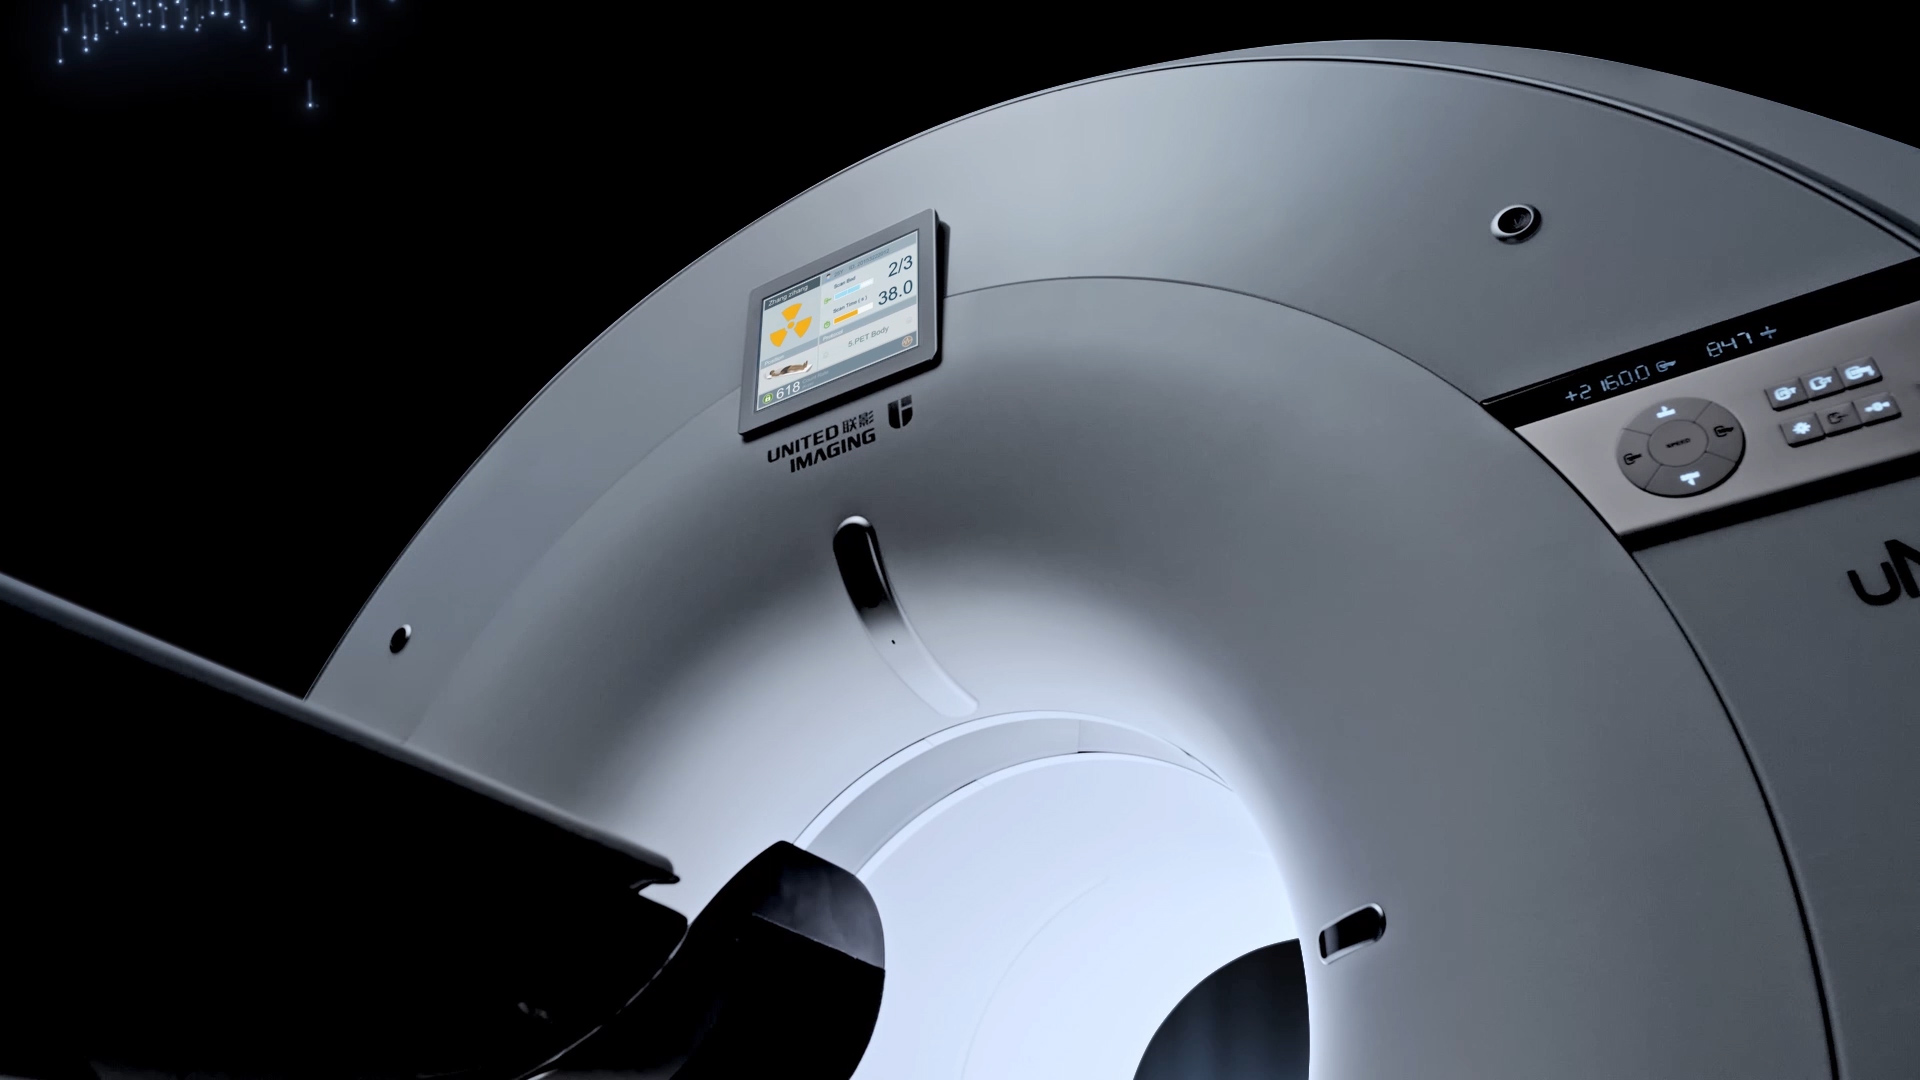

超清显像

2.9mm

超清NEMA分辨率成像

TOF + PSF

微小病灶无以遁形

600 x 600

超大矩阵,高精度超清重建